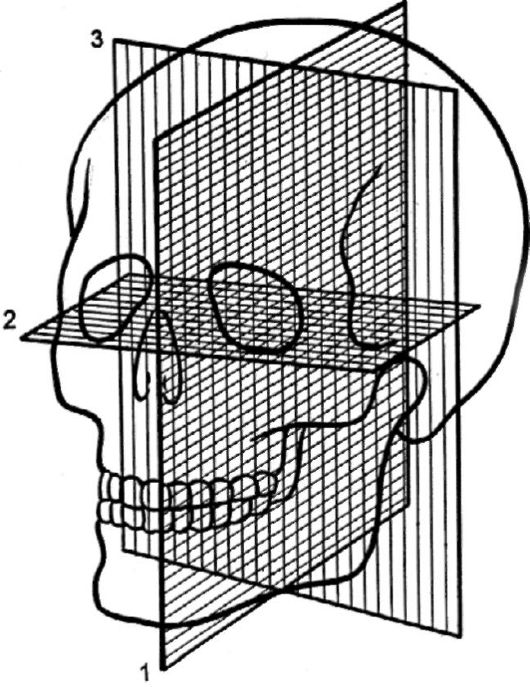

Анатомические изображения срединной сагиттальной линии черепа